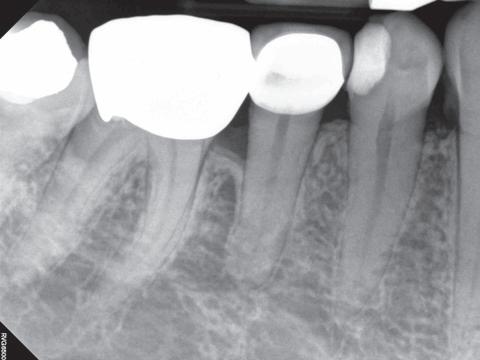

FlashMax P3 har høyere effekt enn “gammeldagse” herdelamper som ofte ligger langt under 1.000 mW/cm2 og herdetid på nærmere minuttet.

FlashMax P3 har 4.000-6.000 mW/cm2 i effekt. Det gir deg muligheten til å gjennomføre trygg lysherding raskere.

Optimalt klinisk resultat

Høyere intensitet gir ikke bare tidsbesparelse, men også større sikkerhetsbuffer for et godt klinisk resultat. Du vil ikke være i tvil om at du har herdet nok. Siden herdetiden er kort vil ikke FlashMax skade pulpa eller forårsake smerte. Det er som med andre lamper viktig å ikke ha mer enn 2mm tykke lag.

Herder alle lysherdende materialer FlashMax P3 herder i området 440-480nm, noe som er det mest vanlige. Alle materialer med Kamferkinon som fotoinitiator herdes med FlashMax P3.